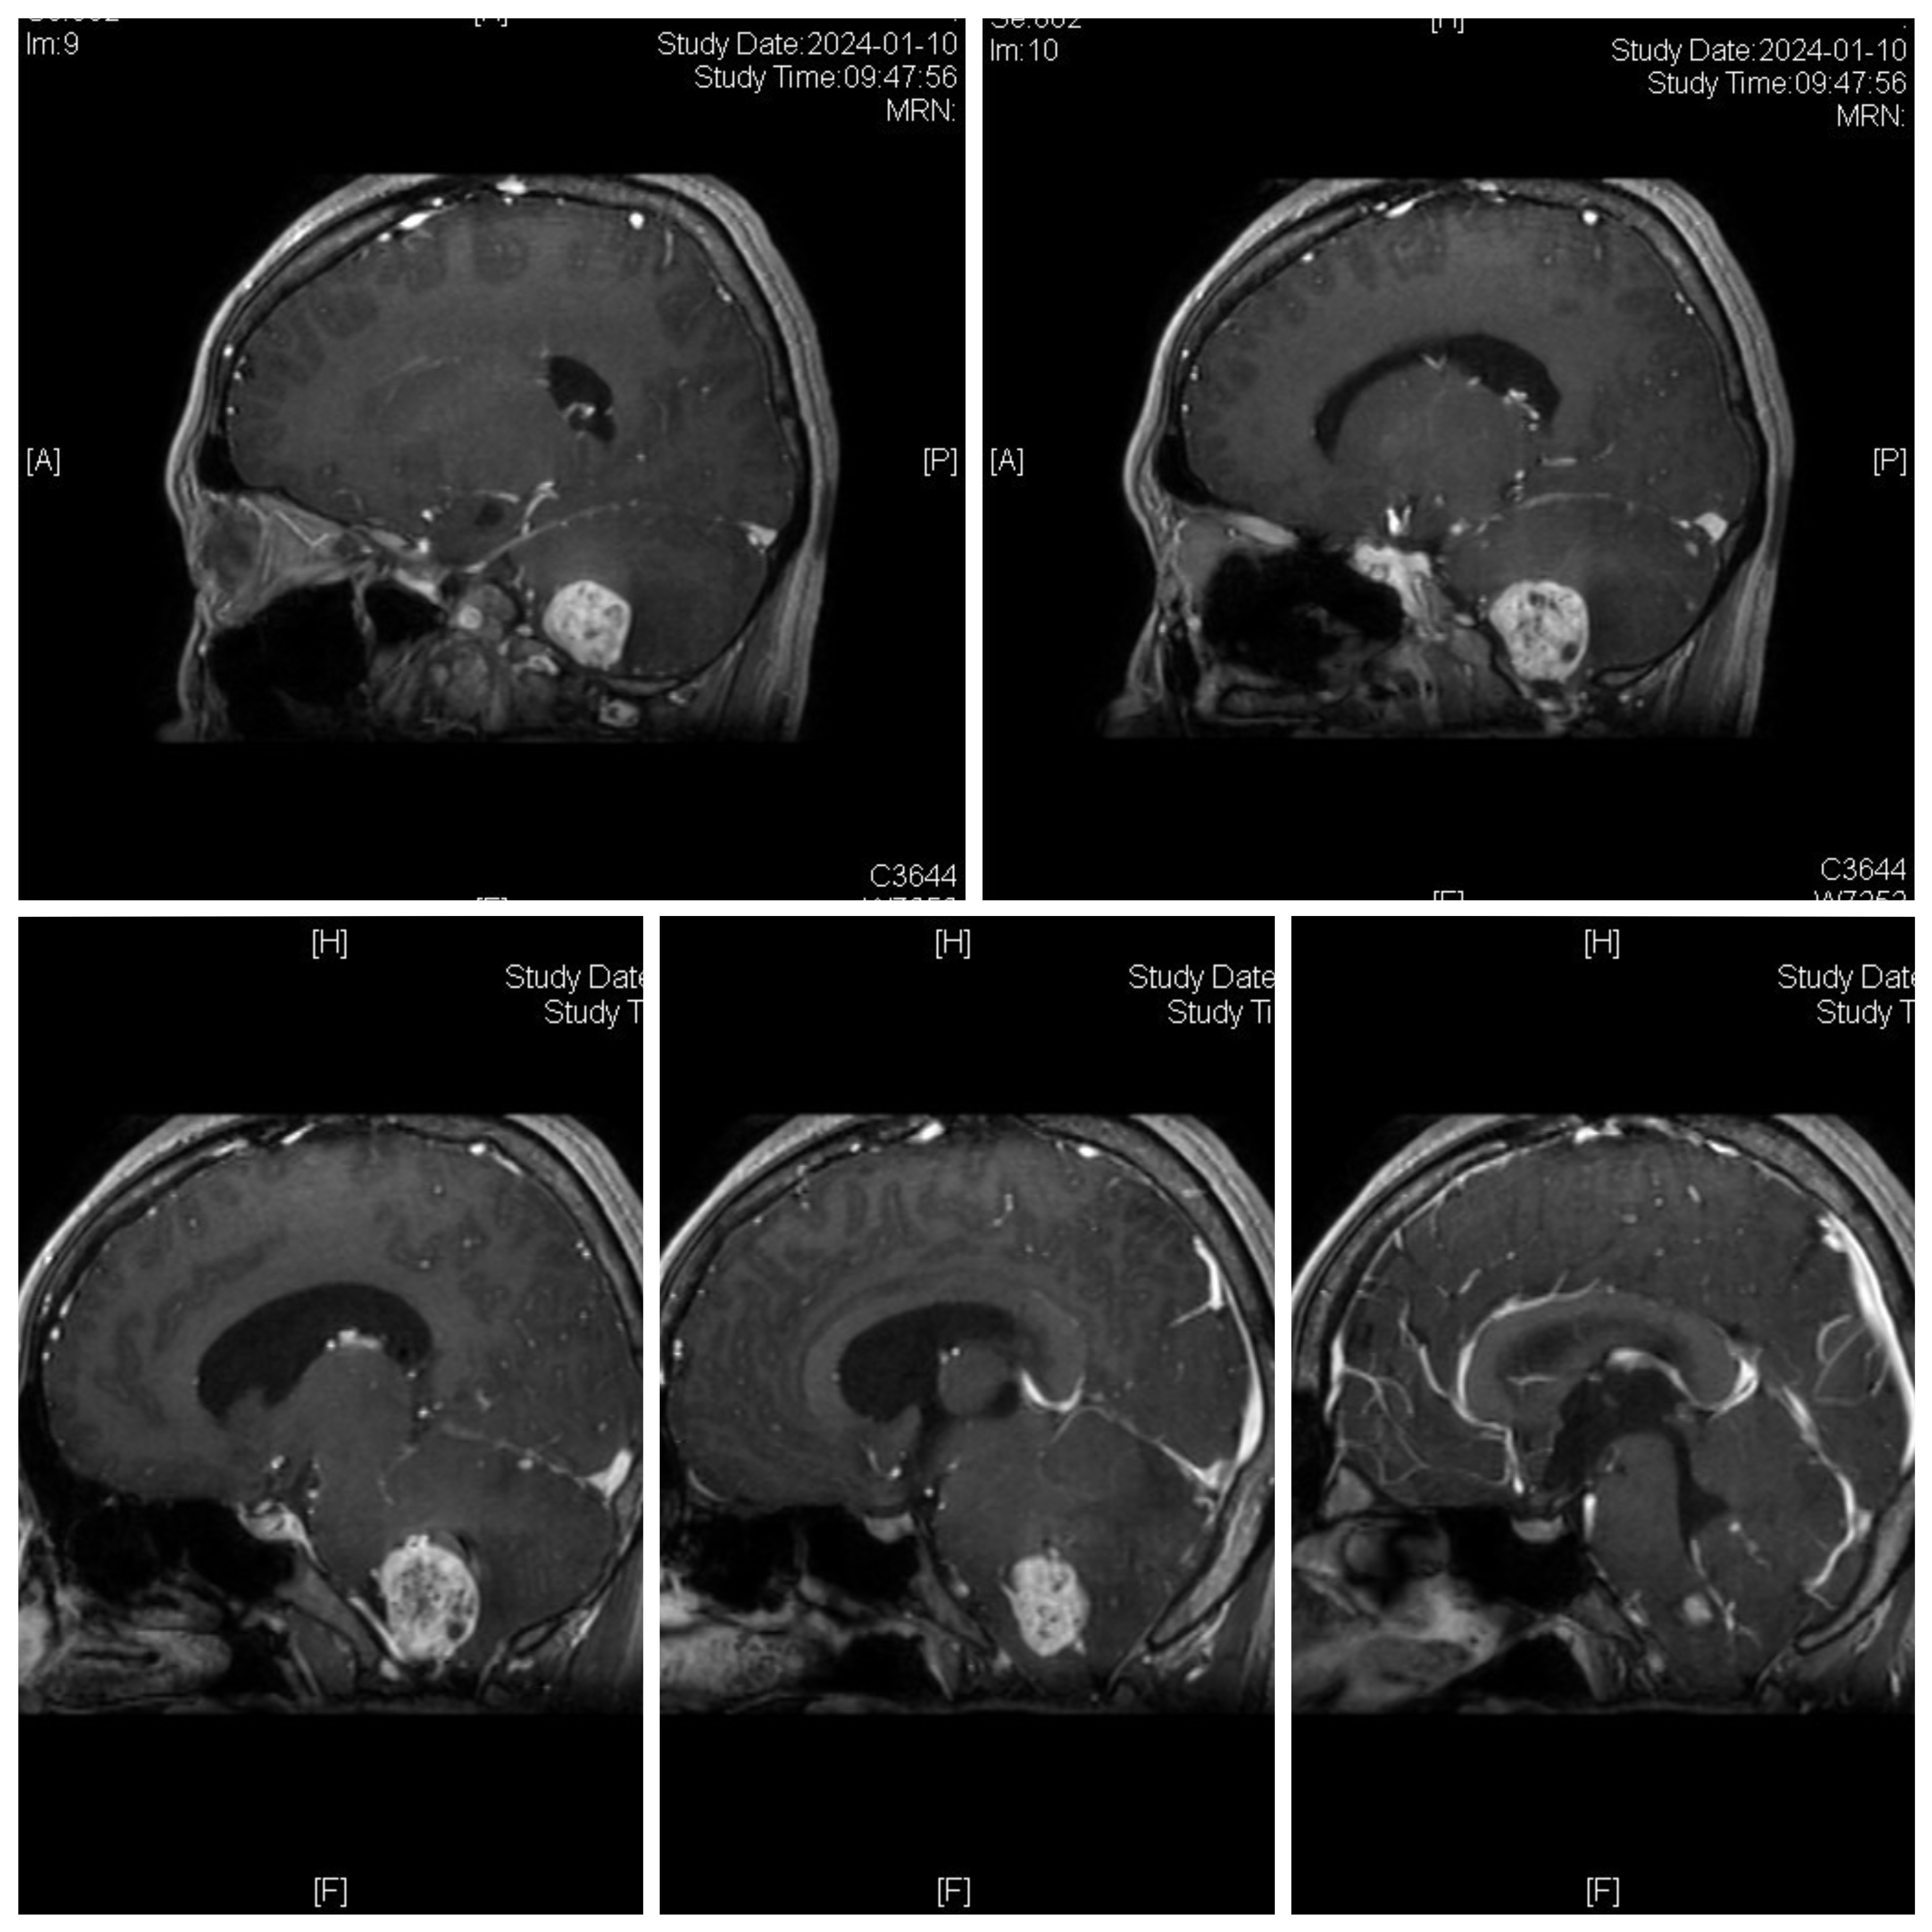

女性患者,26岁,因“间断性头晕1月余。”于2024-01-08入院。

诊断:延髓血管母细胞瘤

von Hippel-Lindau综合征